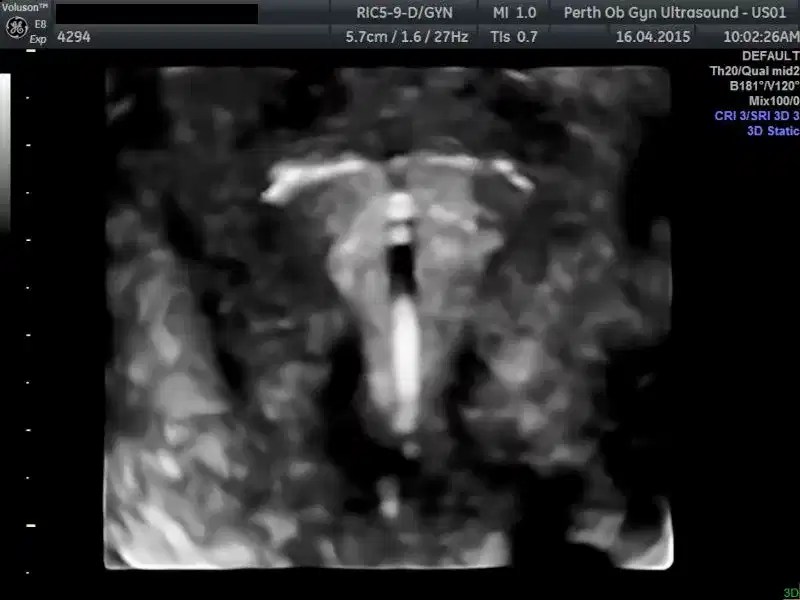

From pogu.com.au

Pelvic Ultrasound POGU What Is A 3D Pelvic Ultrasound Your pelvis is the part of your. What is a pelvic ultrasound? A pelvic 3d ultrasound includes a routine pelvic ultrasound with additional 3d views. A pelvic ultrasound is an imaging test that uses sound waves to make pictures of what's inside your pelvis. During an exam, a technologist uses a special probe to take many. A pelvic ultrasound is. What Is A 3D Pelvic Ultrasound.